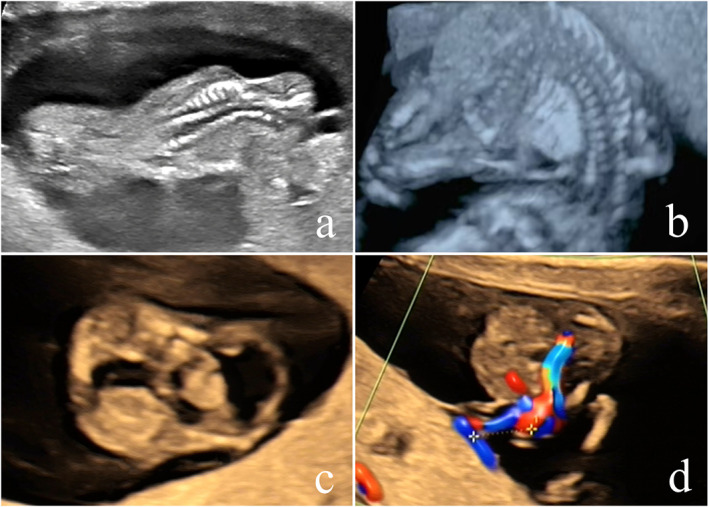

本研究旨在探讨产前超声对妊娠期肢体体壁复合体(LBWC)的诊断价值,提高对LBWC的认识,用于早期超声诊断。回顾性分析郑州大学第三附属医院2014 ~ 2024年107例LBWC(以妊娠早期诊断为主)的超声资料及随访结果。对LBWC的超声特征和胎儿核型进行评价。该队列包括107例LBWC胎儿(90例单胎和17例双胞胎)。典型的超声表现为腹壁严重缺损、重度脊柱后凸、肢体异常、神经管缺损、短脐畸形伴单动脉。值得注意的是,38例清楚地显示胎儿挤压器官位于胚胎外细胞。20例基因检测(7例CNV-seq, 12例CMA, 1例核型)18例结果正常,其余2例病因不明。在4例双胎妊娠中进行了选择性胎儿减位术,成功分娩了健康的新生儿;其余病例均行终止妊娠。LBWC是一种严重的发育畸形,预后很差。超声检查可以在妊娠早期发现,在产前筛查和妊娠管理中显示出关键的诊断价值。

This study aims to explore the diagnostic value of prenatal ultrasound in limb body wall complex (LBWC) during pregnancy and to improve the understanding of LBWC for early ultrasound diagnosis. The ultrasound data and follow-up results of 107 cases of LBWC (predominantly diagnosed in the first trimester) from the Third Affiliated Hospital of Zhengzhou University between 2014 and 2024 were retrospectively analyzed. The ultrasonographic features and fetal karyotype of LBWC were evaluated. The cohort included 107 LBWC fetuses (90 singletons and 17 twins). The typical ultrasonographic features were a major abdominal wall defect, severe kyphoscoliosis, limb abnormalities, neural tube defects, and a malformed short umbilical cord with a single artery. Notably, 38 cases clearly demonstrated fetal extruded organs located within the extraembryonic celom. Genetic testing (7 CNV-seq, 12 CMA, 1 karyotype only) in 20 cases revealed normal results in 18 without clear cause and effect in the remaining two. Selective fetal reduction was performed in four twin pregnancies, resulting in successful delivery of healthy neonate; all remaining cases underwent pregnancy termination. LBWC is a severe developmental malformation with a very poor prognosis. Ultrasonography enables early detection during the first trimester, demonstrating critical diagnostic value in prenatal screening and pregnancy management.